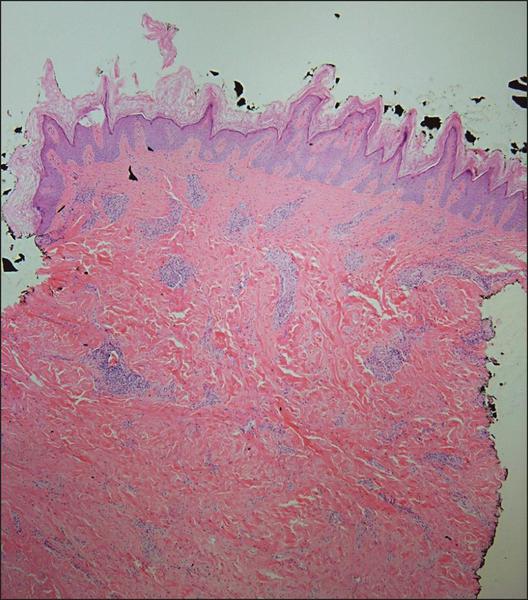

Acanthosis nigricans presents as asymptomatic tan to dark brown velvety plaques usually on the posterior neck and intertriginous areas. It is often a cutaneous manifestation of insulin resistance. Histopathologically, lesions demonstrate hyperkeratosis, papillomatosis, acanthosis, and a thickened dermis. Acanthosis nigricans at the site of repeated insulin injections has been reported at least twice previously in the literature.1,2 The activation of insulinlike growth factor (IGF) receptors due